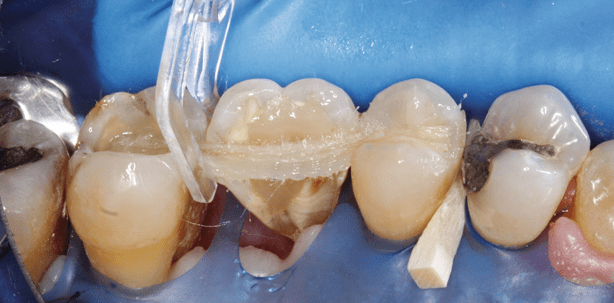

Das Verfahren der Zahnschienung ist am Beispiel eines wurzelamputierten Zahnes 26 nach chirurgisch resektiver Parodontaltherapie eines Patienten mit generalisierter, schwerer chronischer Parodontitis und Diabetes mellitus Typ II veranschaulicht. Die erste Röntgenzahnfilmaufnahme zeigt die Situation nach antiinfektiöser Therapie und vor Endodontie. Diagnostiziert wurde eine Paro-Endoläsion primär-parodontaler Genese mit Furkationsdefekt Grad III sowie von distal und vestibulär sondierbar. Auf der zweiten Röntgenzahnfilmaufnahme ist die Röntgenmessaufnahme unter Kofferdam während der endodontischen Therapie an Zahn 26 dargestellt. Die dritte Röntgenaufnahme zeigt Zahn 26 mit abgeschlossener Wurzelfüllung des mesiovestibulären und palatinalen Wurzelkanals. Der distovestibuläre Wurzelkanal enthält eine medikamentöse Einlage in Form von Kalziumhydroxid. Die Pulpenkammer und der obere Anteil des distovestibulären Wurzelkanals sind mit Kompositmaterial verfüllt, aus dem auch die Deckfüllung besteht (Abb. 1 bis 3). Das vierte Röntgenbild zeigt Zahn 26 nach Wurzelamputation der distalen und palatinalen Wurzel. Intraoperationem erwies sich die Grad-III-Furkation auch mesiopalatinal durchgängig und die palatinale Wurzel als nicht mehr erhaltungsfähig. Die fünfte Röntgenaufnahme zeigt Zahn 26 geschient mit F-Splint-Aid Slim an den Zähnen 25 und 27 (Abb. 4 und 5). Die klinische Fotostrecke zeigt die Vorgehensweise des Zahnschienens mit dem F-Splint-Aid Slim System in der direkten Adhäsivtechnik (Abb. 6 bis 19).

Der besondere Vorteil von F-Splint-Aid Slim ist in der stabilen, geflochtenen Struktur des Splint-Materials zu sehen sowie in seiner praktischen Darreichungsform in der lichtgeschützten Aufbewahrungsflasche. Einen weiteren Vorteil bieten die mitgelieferten Kunststoffspangen „Clip&Splint“, zur Fixierung des Splint-Materials an den Zähnen.7